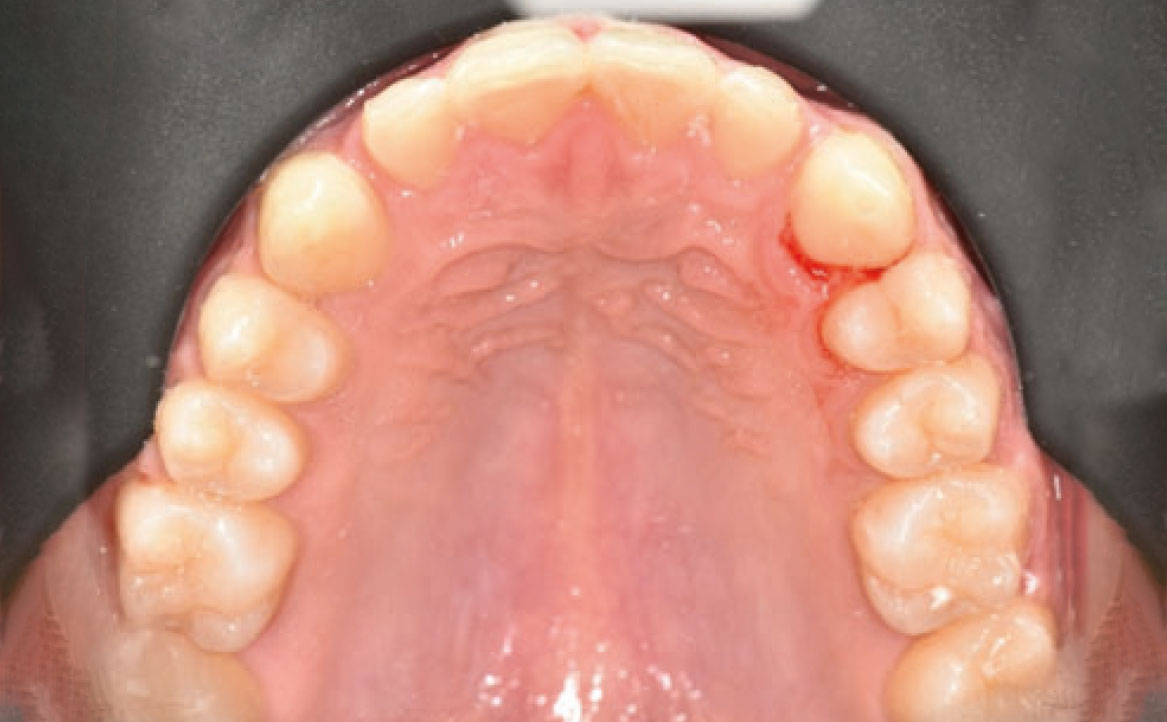

Il paziente si è presentato per la sua prima visita presso il reparto di Odontoiatria e Protesi Dentaria dell’Ospedale Vita-Salute San Raffaele diretto dal prof. E. F. Gherlone. All’esame obiettivo era evidente una malocclusione scheletrica e dentale di classe II associata a morso profondo e lieve affollamento anteriore superiore. In particolare, sono stati segnalati: rapporti occlusali di classe II, morso profondo, perdita di overjet, contrazione dell’arcata superiore e inferiore con leggero affollamento (fig. 1a-f). La richiesta del paziente era quella di migliorare l’estetica dei denti anteriori con allineatori invisibili di tipo Invisalign. Tuttavia, sia il paziente che il genitore sono stati informati che, per ragioni di efficacia e risoluzione del problema, era necessario agire anche a livello di funzionalità e risoluzione della malocclusione.

In primo luogo, sono stati prescritti entrambi gli esami radiografici ortodontici: OPT e teleradiografia latero-laterale del cranio (fig. 2a-b). Successivamente, in accordo con il genitore, è stata concordata una terapia ortodontica in due tempi. L’inizio della terapia è stato effettuato con Carriere Motion ed elastici di classe II, con l’obiettivo di migliorare la classe molare (fig. 2c-e).